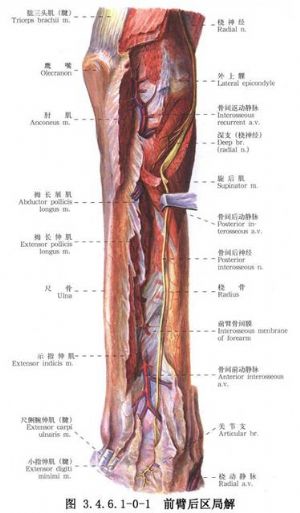

尺桡骨干骨折常见。由于暴力的原因和受伤瞬间肢体的姿式以及肌肉收缩的状态不同,可以发生尺桡骨干双骨折或单骨折。其中,又可发生于不同平面。尺骨干上1/3骨折合并桡骨小头脱位(孟氏骨折Montaggia fracture)。桡骨干下1/3骨折合并下尺桡关节脱位(盖氏骨折Galeazzi fracture)。其中尺桡骨干双骨折占全身骨折的5.41%,为第3位。桡骨骨折占4.23%,为第5位。尺骨骨折占1.05%,为第17位。孟氏骨折占0.63%,为第38位。盖氏骨折占0.35%,为第50位。由于前臂具有旋转功能,一旦发生骨折,除重叠和侧方移位外,尚有严重的旋转移位。因此,对复位的要求较高。如手法复位不满意,难以达到预期功能的恢复,即有手术复位的指征。相关解剖及影像表现见下图(图3.4.6.1-0-1~3.4.6.1-0-6)。